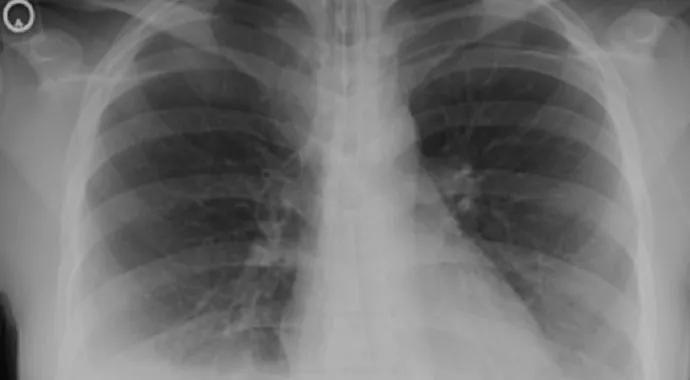

Figure 1. Radiograph showing pleural and pericardial effusion in the case patient.

A 29-year-old woman presented to her primary care physician reporting six weeks of swelling of the fingers and knees, facial rash, and stabbing pain in the chest with breathing. Examination confirmed pleurisy and edema (Figure 1), and lab results revealed anemia, leukopenia and positive ANA findings.